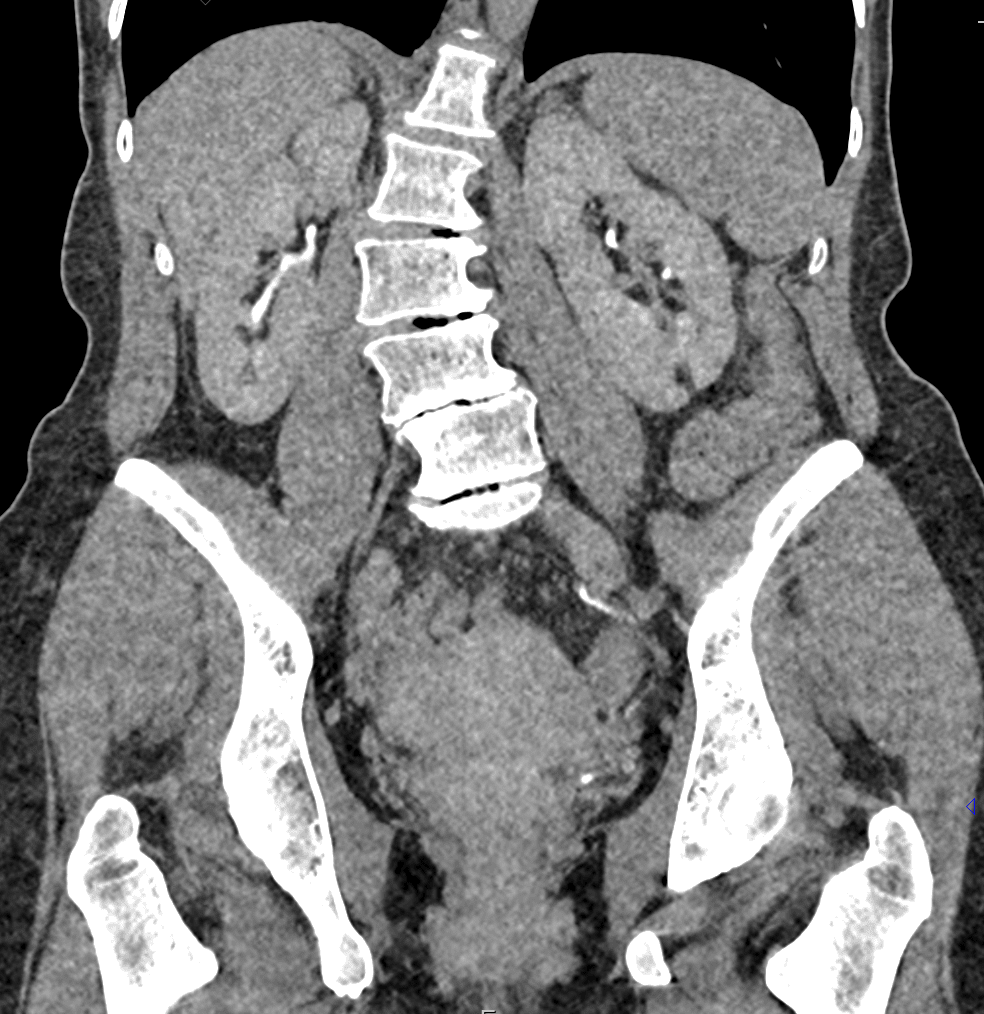

Фотографии и снимки КТ легких без контрастных веществ

Раздел: Визуальный дайджест